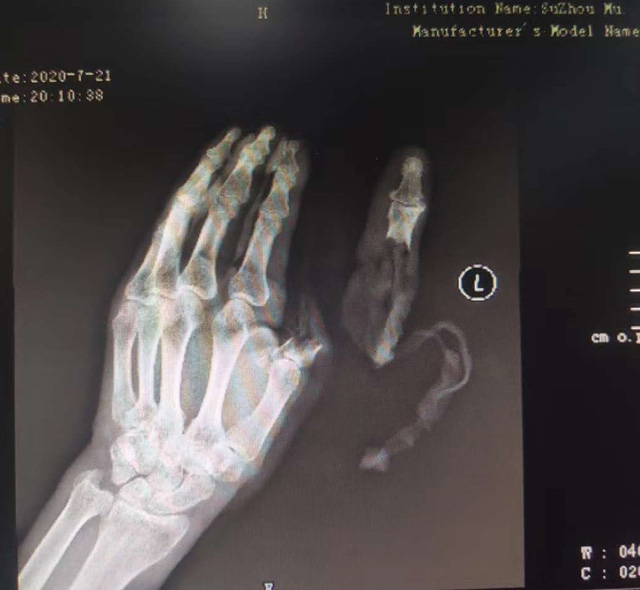

現(xiàn)代快報記者了解到,7月21日下午,這名76歲的老人在家擦拭面粉機時,忘記關(guān)閉電源,結(jié)果抹布被纏進機器,順帶著將老人的手也帶進機器中。老人奮力掙脫,可為時已晚,待將手取出時,已經(jīng)血肉模糊,大拇指在脫落后還被絞入機器軋了一圈……

△老人送醫(yī)時的手部狀態(tài) 蘇州市立醫(yī)院供圖

拇指可以影響一只手40%的功能,為此醫(yī)院立即制定了手術(shù)方案,決定為老人進行斷指再植術(shù),盡力為其保住拇指。由于該患者年紀大、血管彈性差,動脈血管分層也很嚴重,面對重重困難,醫(yī)生在顯微鏡的輔助下,小心翼翼地將血管、神經(jīng)重新吻合,并修復(fù)肌腱、皮膚。經(jīng)過5個多小時努力,最終再植成功。

經(jīng)過和患者反復(fù)溝通,醫(yī)生決定為老人選擇腹部帶蒂皮瓣手術(shù)。即先將發(fā)黑壞死的皮膚清除,再將腹部皮膚覆蓋在手部皮膚缺損處。8月24日,醫(yī)生在老人右下腹設(shè)計了一個皮瓣,將老伯的左手拇指用皮瓣覆蓋。經(jīng)過3周的精心護理,斷指成功“復(fù)活”。9月14日,醫(yī)生將皮瓣蒂部斷開,此時,皮瓣和拇指重新建立了可靠的血運,不僅拇指保住了,長度也和以前的一樣。